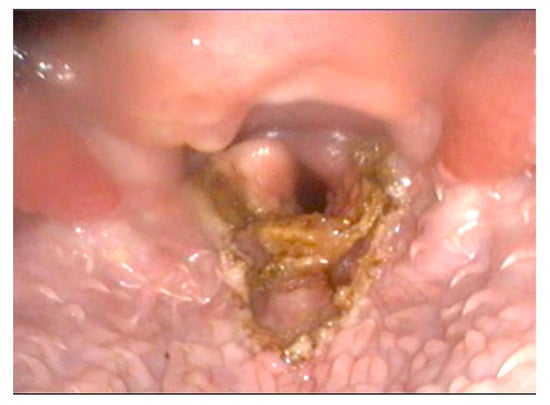

2.1. Surgical Technique